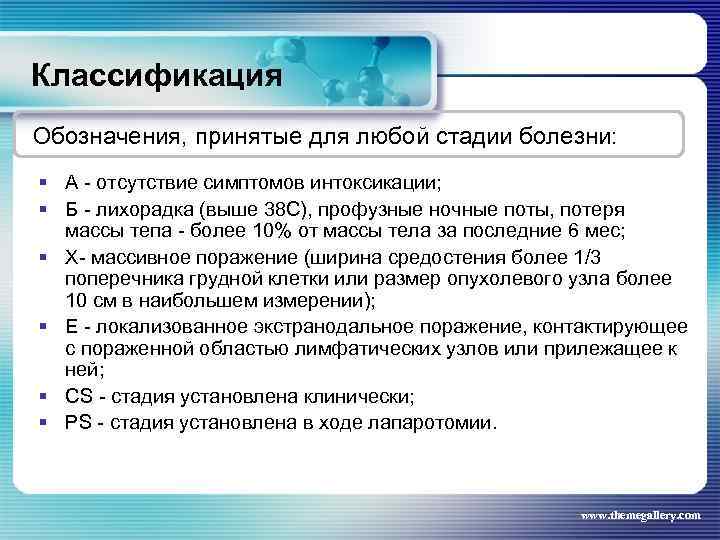

Классификация Обозначения, принятые для любой стадии болезни: § А - отсутствие симптомов интоксикации; § Б - лихорадка (выше 38 С), профузные ночные поты, потеря массы тепа - более 10% от массы тела за последние 6 мес; § Х- массивное поражение (ширина средостения более 1/3 поперечника грудной клетки или размер опухолевого узла более 10 см в наибольшем измерении); § Е - локализованное экстранодальное поражение, контактирующее с пораженной областью лимфатических узлов или прилежащее к ней; § CS - стадия установлена клинически; § PS - стадия установлена в ходе лапаротомии. www. themegallery. com

Классификация Обозначения, принятые для любой стадии болезни: § А - отсутствие симптомов интоксикации; § Б - лихорадка (выше 38 С), профузные ночные поты, потеря массы тепа - более 10% от массы тела за последние 6 мес; § Х- массивное поражение (ширина средостения более 1/3 поперечника грудной клетки или размер опухолевого узла более 10 см в наибольшем измерении); § Е - локализованное экстранодальное поражение, контактирующее с пораженной областью лимфатических узлов или прилежащее к ней; § CS - стадия установлена клинически; § PS - стадия установлена в ходе лапаротомии. www. themegallery. com